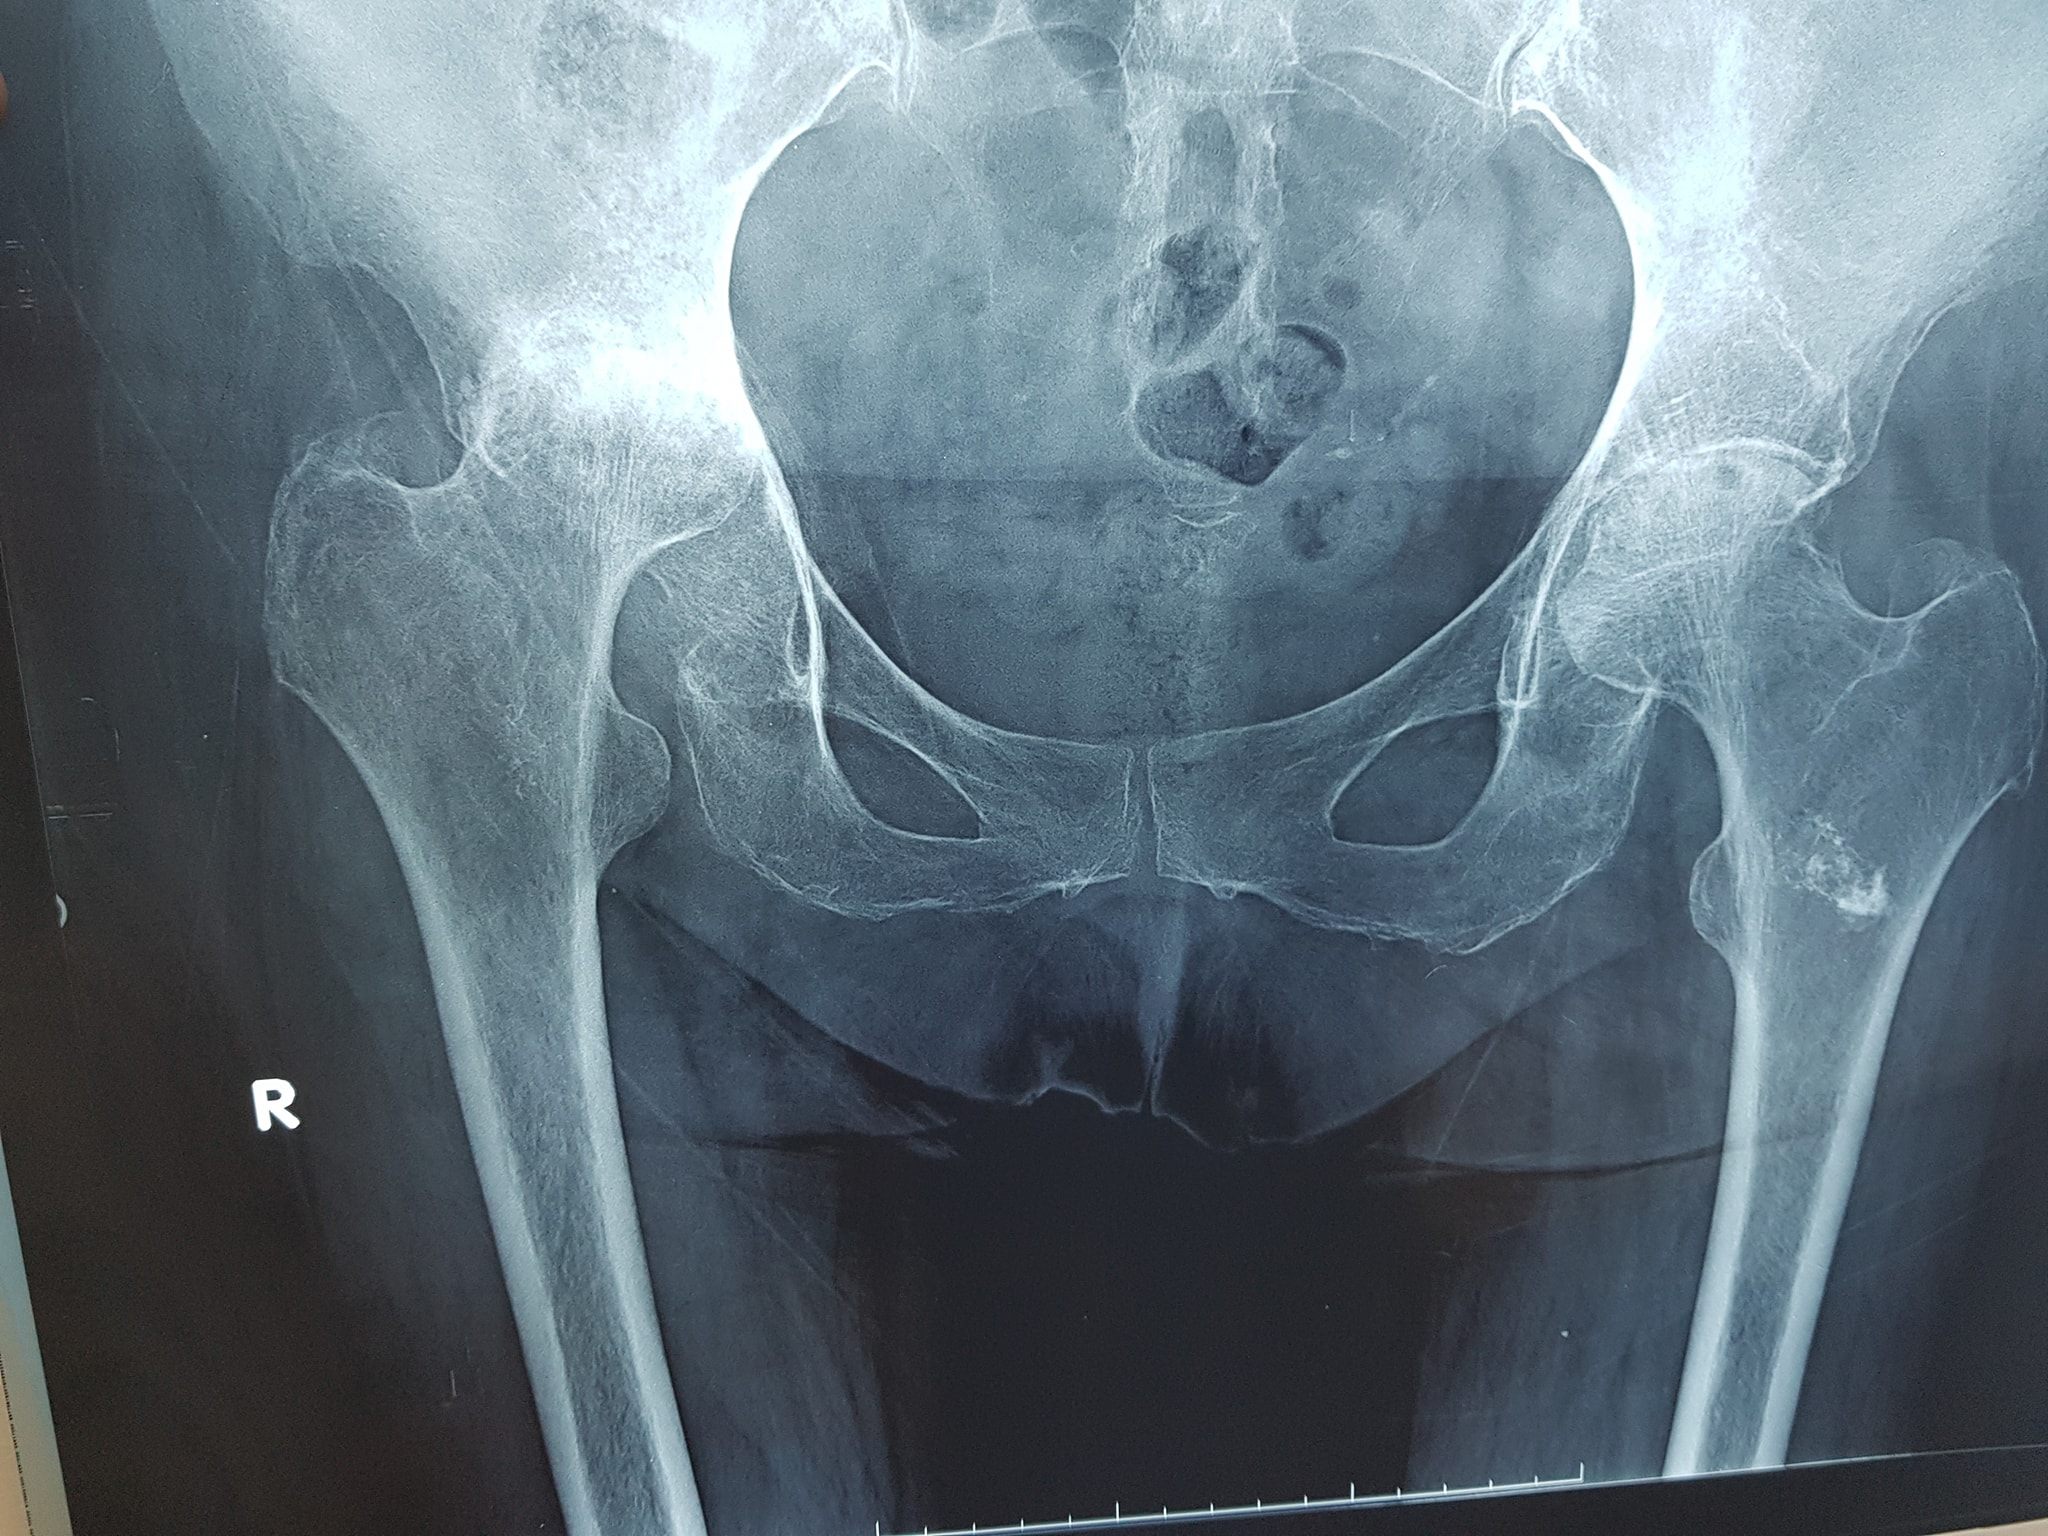

علاج كافة أمراض العظام

كافة انواع الكسور وعلاجها

علاج خلع الورك الولادي بكافة ا